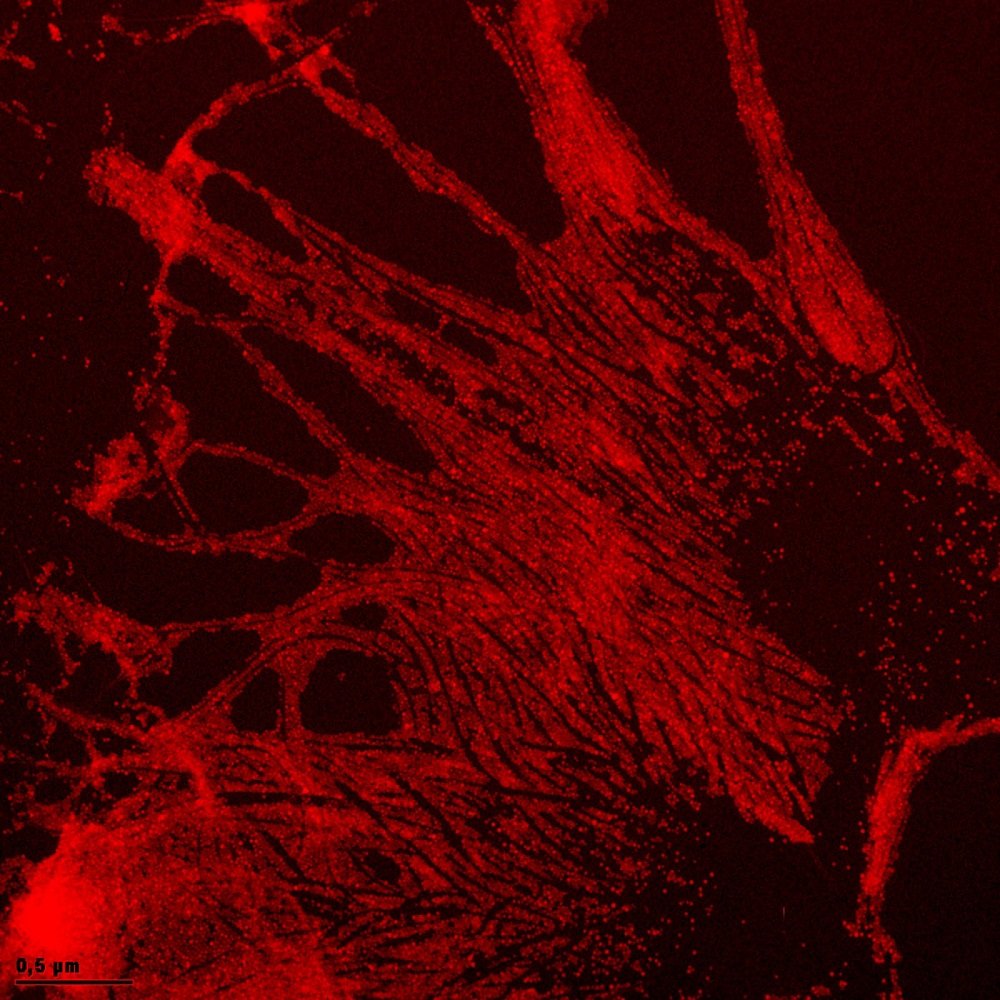

“Se trata de microprobetas con arreglos nanométricos de oro, nanopartículas metálicas coloidales (sustancias líquidas) y cristales fotónicos de silicio poroso”, indicó.

Las microprobetas, que son orificios micrométricos formados por depósitos de películas de oro muy delgadas, se rellenan con nanopartículas metálicas coloidales que detectan diferentes sustancias, de preferencia orgánicas.

Mediante métodos químicos y electroquímicos, la pulverización catódica y la ablasión láser, De la Mora Mojica y sus colaboradores sintetizan materiales nanométricos y caracterizan sus propiedades ópticas a fin de establecer el más apropiado para determinar la presencia de moléculas orgánicas específicas.

Los universitarios esperan probar las microprobetas con arreglos nanométricos de oro, las nanopartículas metálicas coloidales y los cristales fotónicos de silicio poroso para decidir cuál de estos biosensores se puede modificar con miras a mejorar su respuesta.